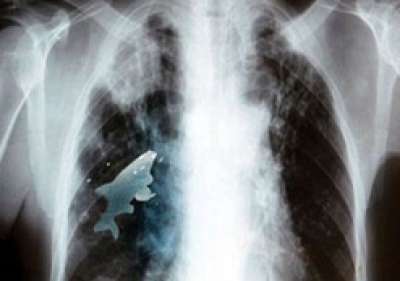

وقال الأطباء بأن الأطفال عادة ما يبتلعون الأسماك الصغيرة أثناء سباحتهم في الأنهار والمستنقعات، إلا أن السمكة الصغيرة التي بلغ طولها نحو 11 سم التي ابتلعها الطفل أنيل أخذت طريقها إلى رئته اليمني بدلاً من وصولها إلى معدته، مما تسبب في تدهور صحته وشعوره بالاختناق وبألم في الصدر،استدعى تصوير صدره أشعاعياً والذي كشف عن وجود جسم متحرك داخل الرئة.

وبعد اخضاع الطفل لمزيد من الفحوص بواسطة جهاز الماسح الضوئي اتضح أن وجود سمكة حية تتحرك في رئته اليمنى.